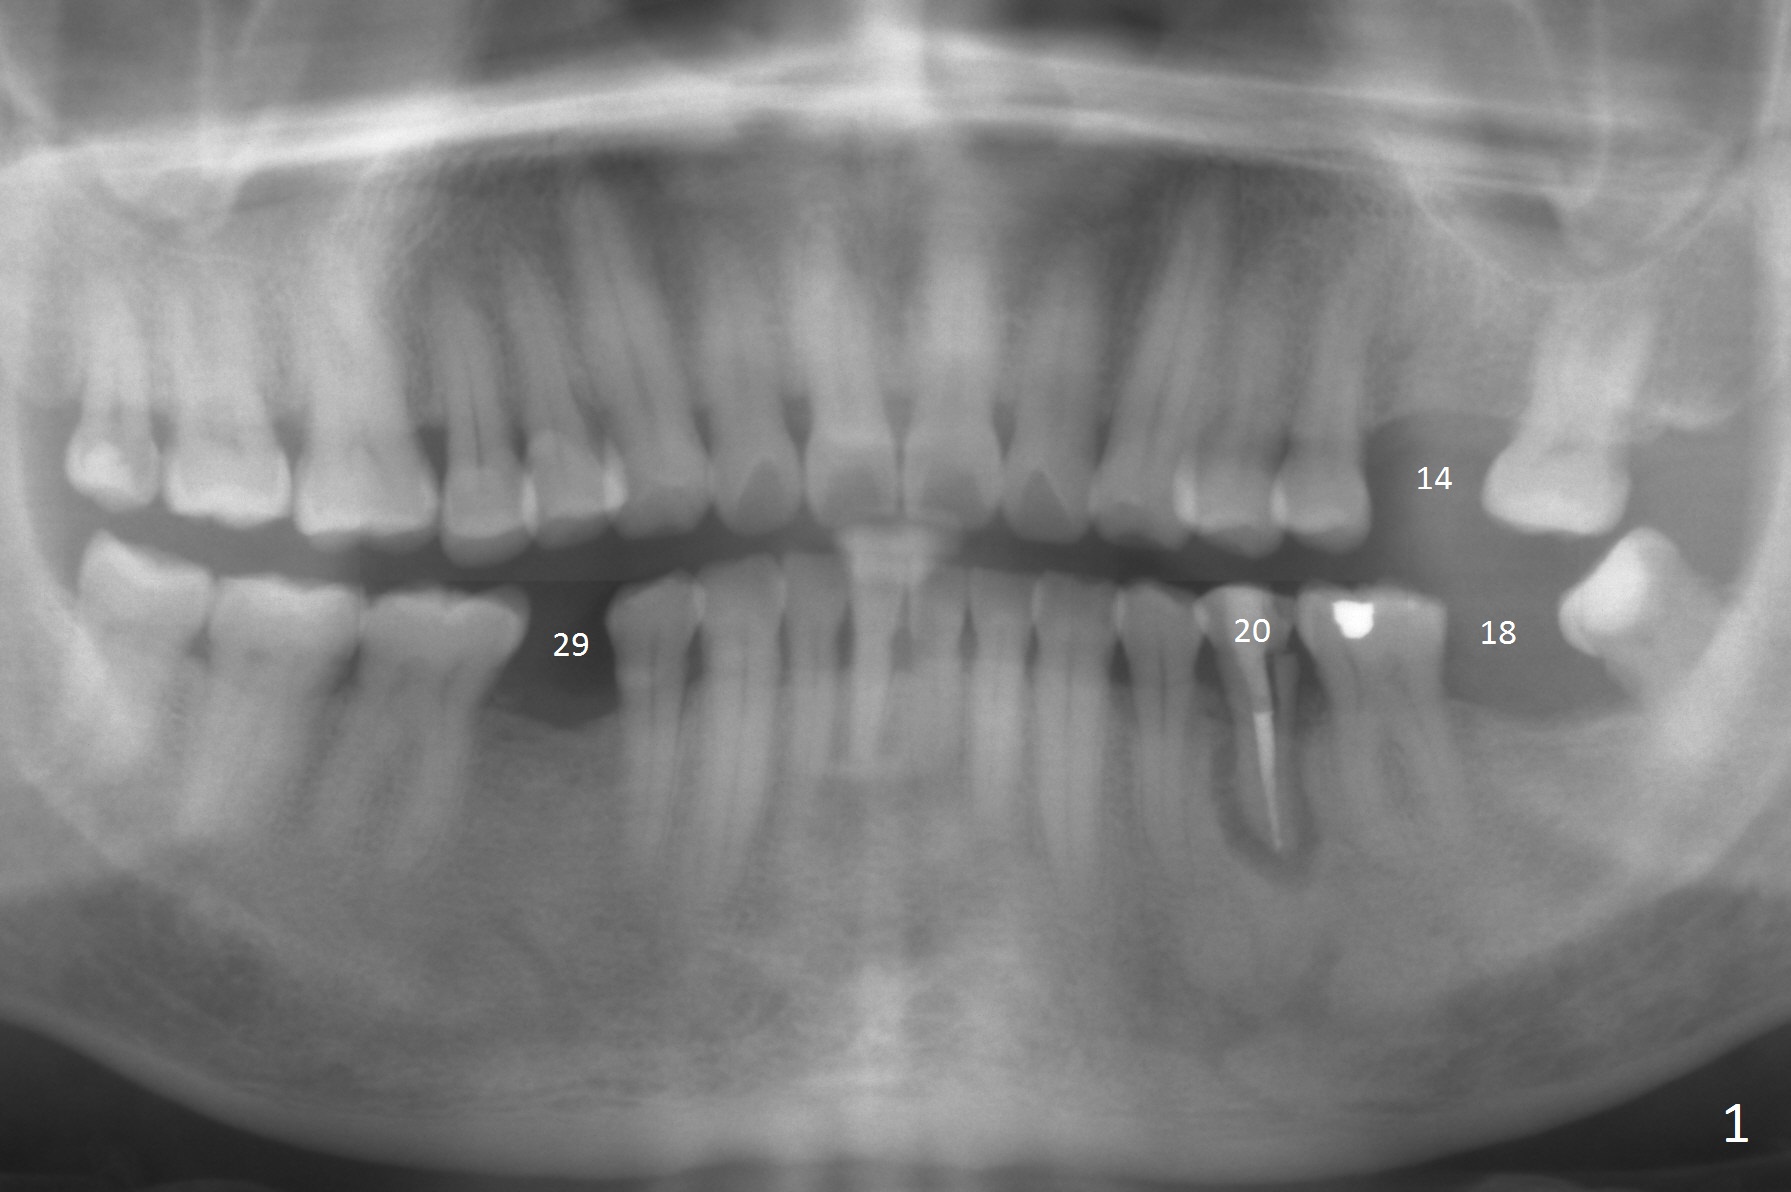

A 53-year-old man (probably bruxer, long roots) has 3 missing teeth (Fig.1 #14,18,29) and 1 fractured tooth (Fig.2 #20).  The fractue is associated with deep buccal pockets.  The buccal plate is most likely defective.  After extraction (Metronidazole), start osteotomy lingual and mesial (Fig.3 red long arrow) to reduce damage to the Mental Loop (Fig.4 red dashed line).  Damage to the Incisive Canal (yellow dashed line, the continuum of the Inferior Alveolar Canal after giving off the Mental Loop) is less significant.  Since the defect is long, use the longest implant and place it deep.  A long abutment (7 mm, green) with 5 mm cuff (pink) is required.  To have sufficient buccal gap for bone graft and probably membrane, the smallest two-piece implant is necessary (3.8 mm).